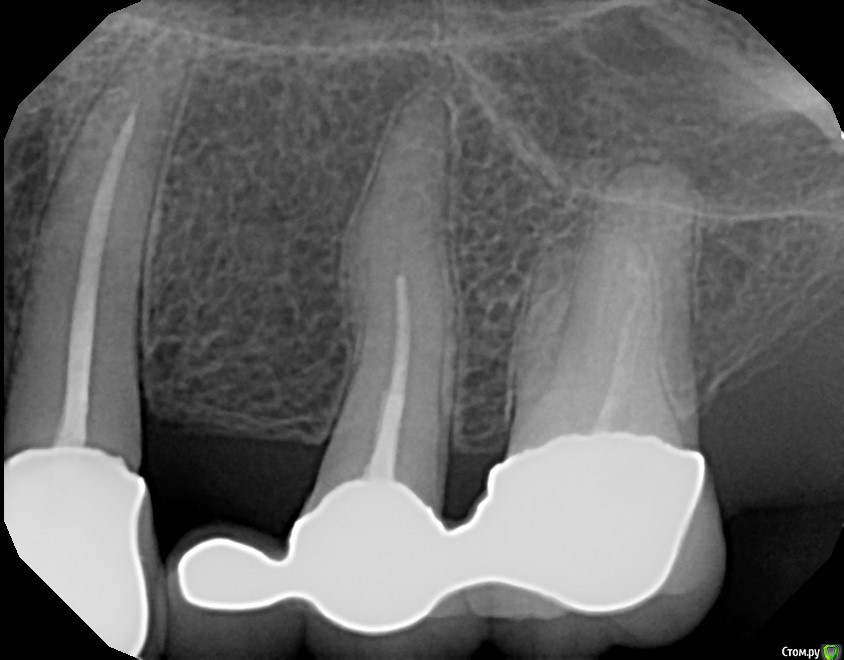

Dirina12 Опубликовано 11 июля, 2017 Поделиться Опубликовано 11 июля, 2017 Сегодня лечили зуб (номер 14), запломбировал 2 канала, а 3-й не мог найти (делал со снимками и микроскопом). Что делать? Будет ли болеть зуб? И почему не мог найти ?Ето нормально, что не может найти канал или плохой врач?На снимке самый крайний зуб. Ссылка на комментарий

Dirina12 Опубликовано 11 июля, 2017 Автор Поделиться Опубликовано 11 июля, 2017 Здесь ( зуб номер 2) тоже видно что 2 канала запломбировано, а 3-го нет. Как так? Ссылка на комментарий

Ponchik Опубликовано 12 июля, 2017 Поделиться Опубликовано 12 июля, 2017 2 канала запломбировано, а 3-го нет. Третий есть. Внимательнее посмотрите. Вот есть ли четвертый не видно. а 3-й не мог найти (делал со снимками и микроскопом). Вот если бы не сказал и залепил, "как есть" - тогда плохой. И почему не мог найти ? Этот вопрос надо задать вашему зубу - почему каналы не в типичном месте? Почему облитерированы? Если нет доверия к врачу и Вы ищите ошибки в каждом его действии - меняйте врача. Ссылка на комментарий